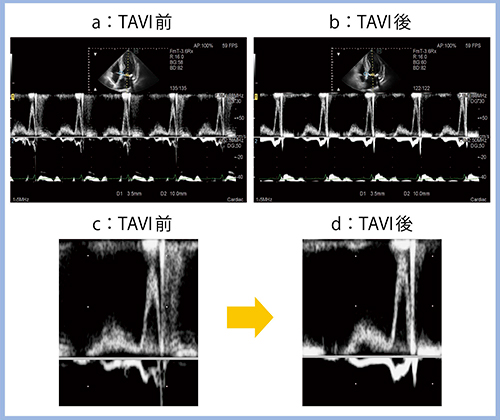

また,経カテーテル大動脈弁留置術(TAVI)を施行した症例について,術前後でTE-e’を計測した(図2)。E波とe’波では,e’波の方が先に起こるのが正常4)であるが,本症例の場合,TAVI術前(図2a,c)に先に血液が流入し始めている。すなわち,吸引によって流入しているのではなく,高い左房圧によって押し出された血液が流入しており,明らかに異常な病態である。しかし,TAVIによって左室後負荷を取り除いたところ,正常な血流パターンとなった(図2b,d)。こうした術前後の変化も,Dual Gate Dopplerにてひと目で確認することができる。

図2 Dual Gate DopplerによるTE-e’の計測

(TAVI前後の変化)